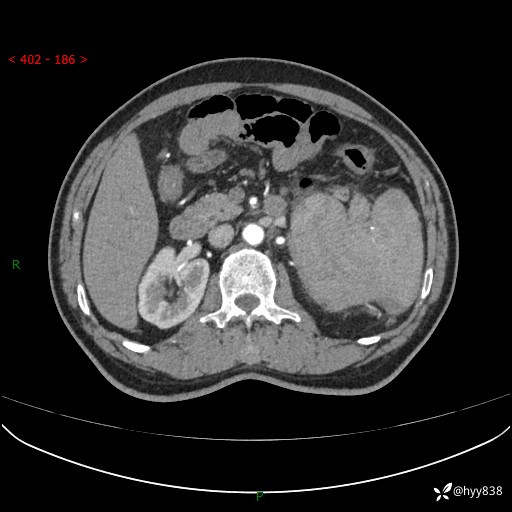

上腹部CT平扫

增强(动脉期+静脉期)